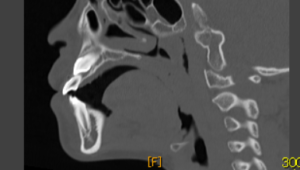

「上顎犬歯埋伏のCT画像」

川崎歯科(大阪府吹田市)